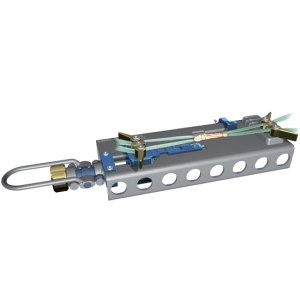

Tape Locking Screw (TLS)

Unique to the TLS system is its hand reamed retrograde tunnels which gives the possibility to fine-tune tunnel position per-operatively. As a result, studies have shown the TLS to produce less post-operative pain than traditional techniques and other short graft procedures² whilst also producing excellent long-term patient outcomes.

Re-rupture rates are reported at anywhere between 1.9%³ and 6% at 2 years in various independent peer reviewed papers.⁴ In addition, graft preparation is simple and versatile, allowing the surgeon to adjust graft size slightly to match the patient anatomy.